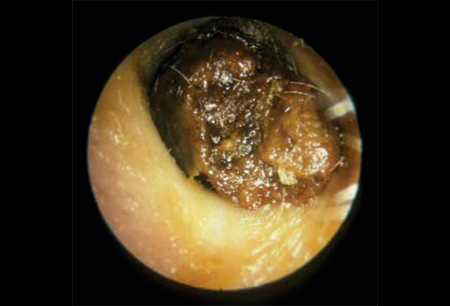

- Pushes Wax Deeper: Cotton swabs typically push the cerumen deeper into the ear canal, past the self-cleansing area. This can lead to impaction, where the wax becomes blocked and causes symptoms like hearing loss, pain, ringing (tinnitus), or a feeling of fullness.

If you experience persistent symptoms like decreased hearing, pain, dizziness, discharge, or believe you have an earwax blockage (impacted cerumen), professional removal by an ENT specialist (Otolaryngologist) or a trained primary care provider is the safest and most effective solution.

- Manual Removal: Using specialized, curved instruments (curettes or forceps) to scoop or grasp the wax.